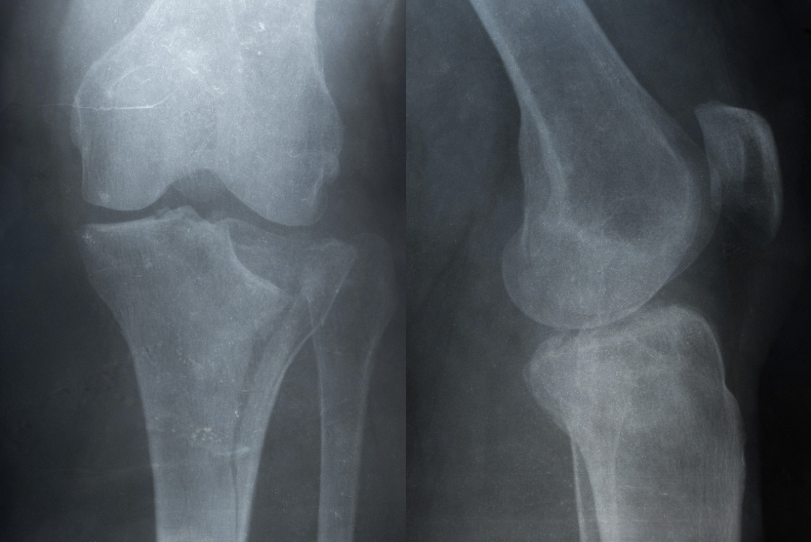

Facing a recovery process after a tibia fracture requires a structured, progressive, and highly conscious approach. For an advanced athlete training in a home gym, returning to full functionality cannot be left to chance, but must follow precise principles of physiological adaptation and controlled loading.

The transition from assisted walking to returning to the squat represents a delicate phase, where every technical decision directly impacts the quality of recovery. Using appropriate tools such as racks and certified barbells allows for safe and effective modulation of the training stimulus.

The first goal after a tibial fracture is restoring load-bearing capacity under controlled conditions. The initial phase is characterized by limited movement and the use of support aids, but it is precisely at this stage that the foundation for an effective gym-based rehabilitation is established.

Bone responds to mechanical stimuli through a remodeling process. This means that a well-managed progressive load stimulates regeneration and structural adaptation, improving the tibia’s resistance over time.

The tibia responds positively to controlled compressive loads. This makes exercises such as squats and lunges particularly effective, provided they are introduced at the appropriate stage of recovery.